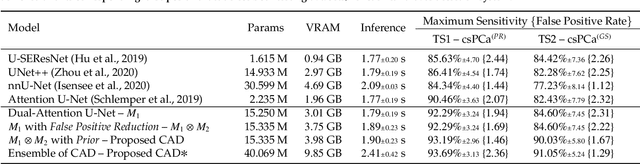

End-to-end Prostate Cancer Detection in bpMRI via 3D CNNs: Effect of Attention Mechanisms, Clinical Priori and Decoupled False Positive Reduction

We present a novel multi-stage 3D computer-aided detection and diagnosis (CAD) model for automated localization of clinically significant prostate cancer (csPCa) in bi-parametric MR imaging (bpMRI). Deep attention mechanisms drive its detection network, targeting multi-resolution, salient structures and highly discriminative feature dimensions, in order to accurately identify csPCa lesions from indolent cancer and the wide range of benign pathology that can afflict the prostate gland. In parallel, a decoupled residual classifier is used to achieve consistent false positive reduction, without sacrificing high sensitivity or computational efficiency. Furthermore, a probabilistic anatomical prior, which captures the spatial prevalence of csPCa as well as its zonal distinction, is computed and encoded into the CNN architecture to guide model generalization with domain-specific clinical knowledge. For 486 institutional testing scans, the 3D CAD system achieves $83.69\pm5.22\%$ and $93.19\pm2.96\%$ detection sensitivity at 0.50 and 1.46 false positive(s) per patient, respectively, along with $0.882$ AUROC in patient-based diagnosis $-$significantly outperforming four state-of-the-art baseline architectures (U-SEResNet, UNet++, nnU-Net, Attention U-Net) from recent literature. For 296 external testing scans, the ensembled CAD system shares moderate agreement with a consensus of expert radiologists ($76.69\%$; $kappa=0.511$) and independent pathologists ($81.08\%$; $kappa=0.559$); demonstrating strong generalization to histologically-confirmed malignancies, despite using 1950 training-validation cases with radiologically-estimated annotations only.